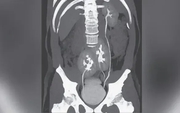

• "Bác sĩ ơi cứu em, nhưng... cho em về ăn Tết xong mổ được không": Lời cầu khẩn khiến bác sĩ khoa Thận-Tiết niệu và Nam học lặng người trước thềm năm mới

"Bác sĩ ơi cứu em, nhưng... cho em về ăn Tết xong mổ được không": Lời cầu khẩn khiến bác sĩ khoa Thận-Tiết niệu và Nam học lặng người trước thềm năm mới

Sức khỏe -

Các bác sĩ cũng nhấn mạnh, người dân không nên trì hoãn điều trị vì bất kỳ lý do nào, kể cả công việc hay chi phí, bởi khi thận đã bị tổn thương nặng, việc điều trị sẽ phức tạp và tốn kém hơn rất nhiều.